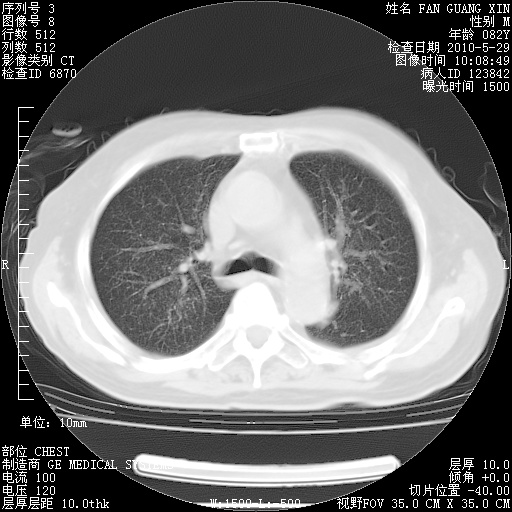

再治疗10天后的肺部CT

阅读此次胸部CT,肺间质渗出性改变较入院时有吸收。目前从体温、白细胞、中性分叶明显增高,肯定存在细菌感染(发生医院感染哦,若无消化道及泌尿系统等感染的依据,肺部感染可能大)。若你院头孢哌酮舒巴坦钠耐药率较高,同意你的方案,若48小时体温仍高,可考虑使用碳青霉稀类抗菌药物,同时可予超声雾化、注意滴数时加大液体量。白蛋白33.30g/L较低哦,需加强营养等支持治疗。

从白细胞总数和中性比例看好像合并感染。肺部纹理好像比上次多,支气管炎?其他感染?

肺部体征:呼吸25次/分,心率100次/分,呼吸音增粗。无干湿罗音。

血常规:15.36×10 [sup]9[/sup]/L  N0.92  L0.036  M0.045 ESR 27mm/h。

血生化:白蛋白33.30g/L  球蛋白23.67g/L  CRP 32.82mg/L 肝肾功能正常。电解质正常。